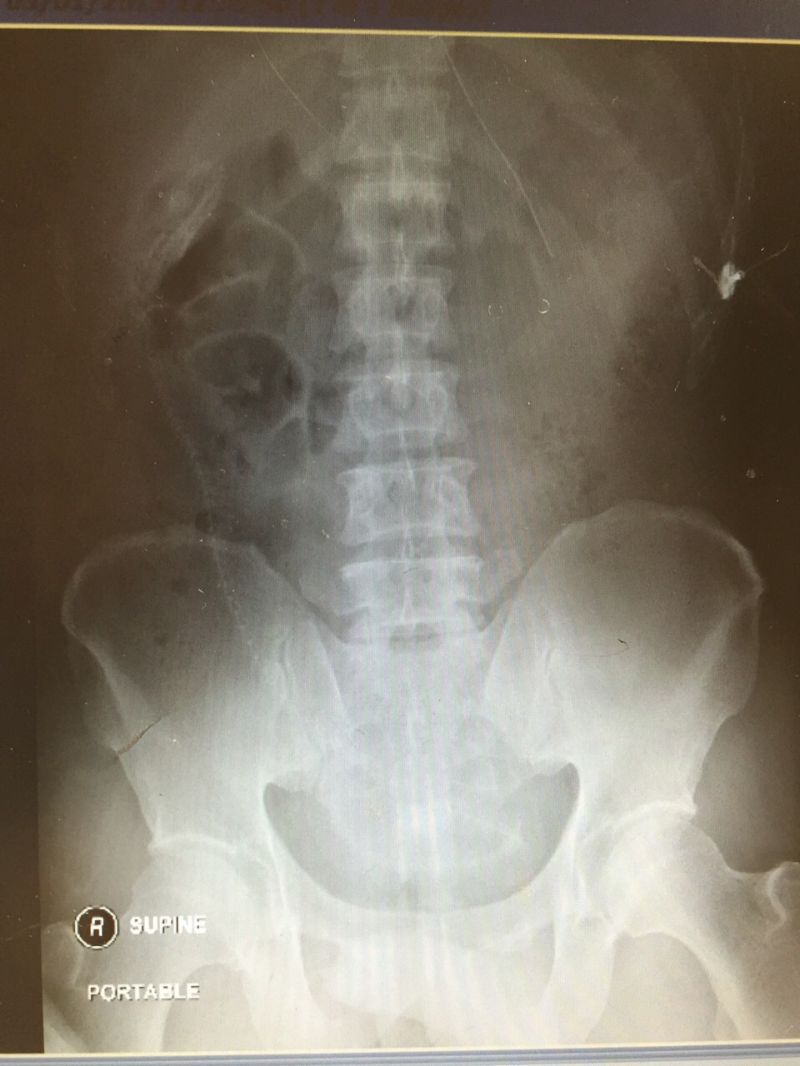

gif_animation ウナギでアナルオ●ニーしていた男の恐ろしい末路。男はお腹(腸内)に激しい痛みを訴え、病院を訪れた。それは手術により取り出され…。[4]images